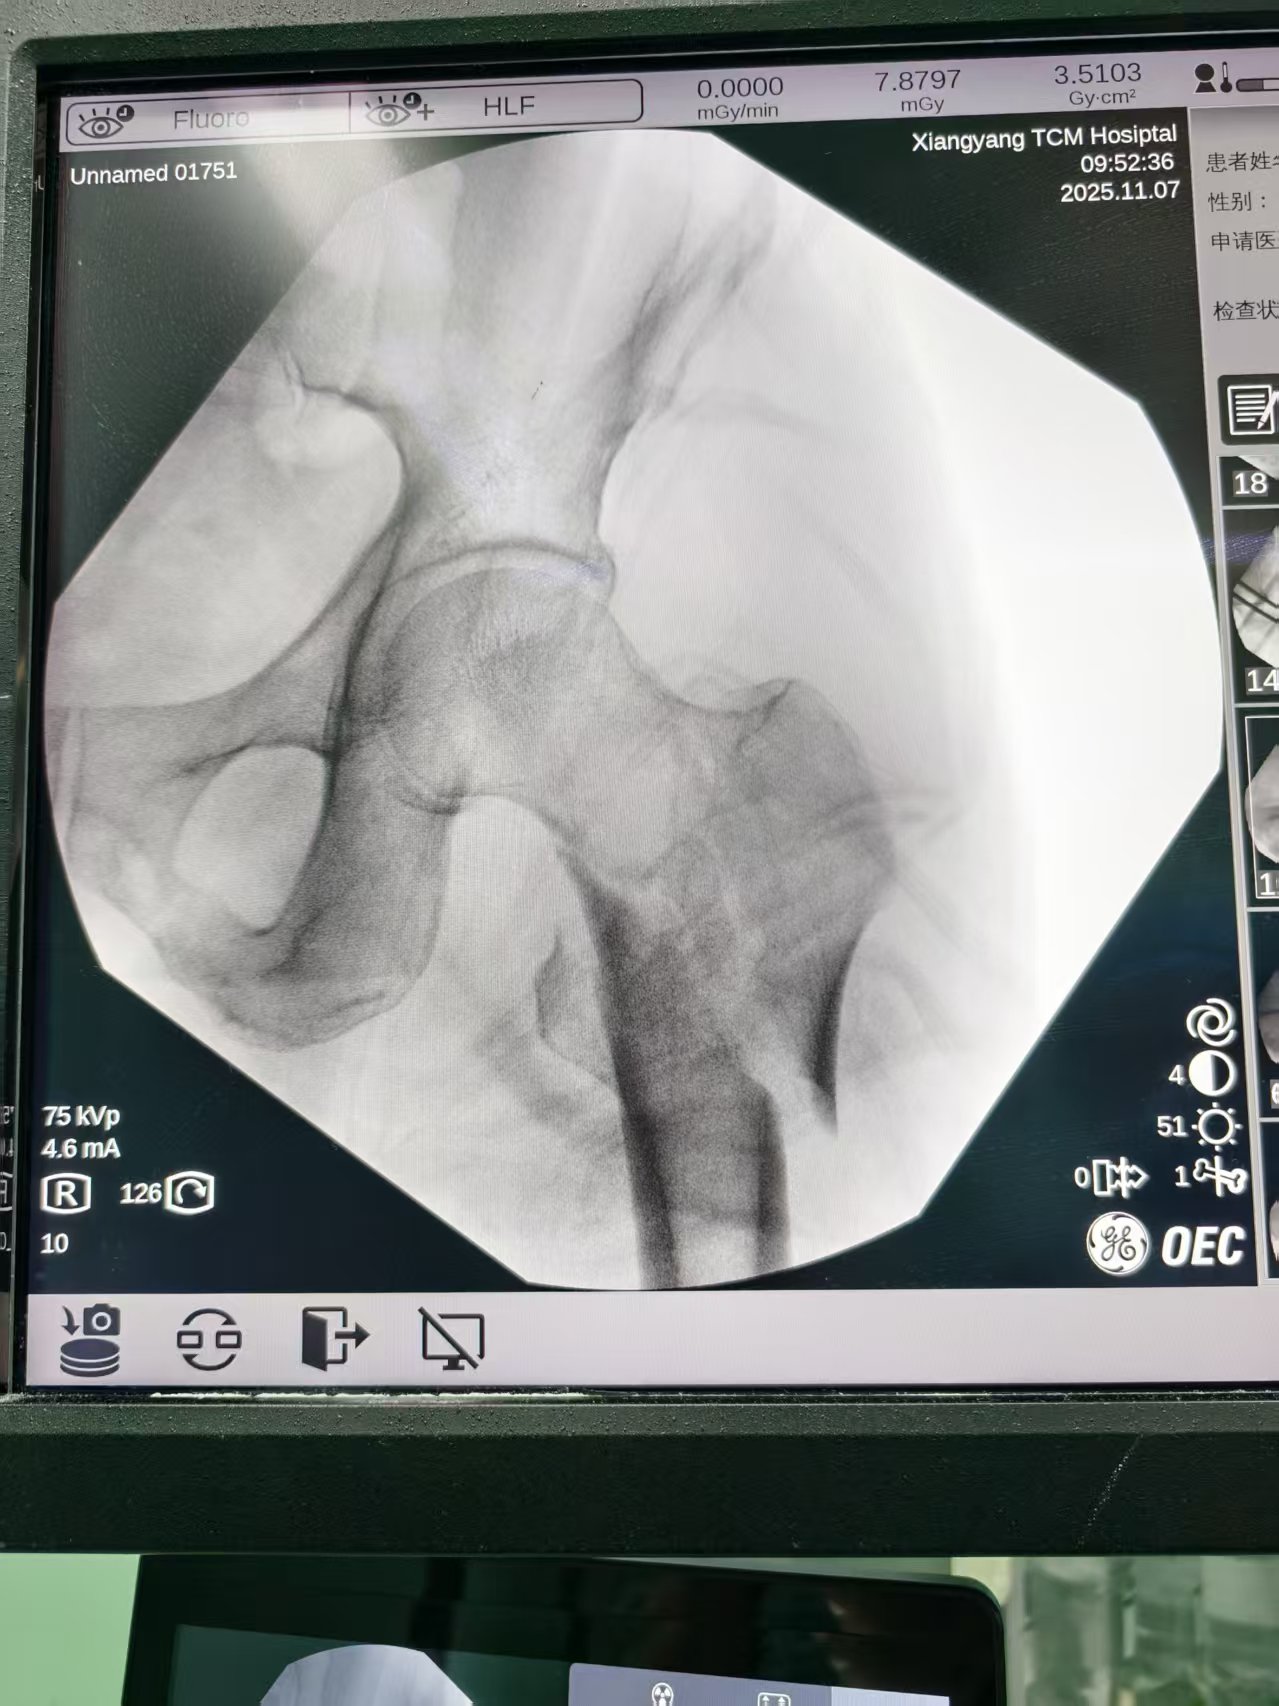

该院创伤骨二科主任孙志波接诊了李爷爷,查体发现患者左下肢呈外旋畸形,左侧腹股沟处按压痛及大转子处叩击痛明显,髋关节活动受限,拍片显示右侧股骨转子间错位1.2厘米,遂诊断为股骨转子间粉碎性骨折,需要立即手术治疗,在与患者及其家属沟通并取得同意后,孙志波将李大爷收治入院。

术中,张俊松将患肢置于牵引架上,通过牵引解除骨折断端的移位,随后采用手法复位将股骨转子骨骨折处复原,通过C型臂实时透视定位,将特制的髓内钉精准置入股骨髓腔,利用螺旋刀片锁定骨折端,实现骨折复位与固定的双重目标。整个手术过程出血量控制在50毫升以内,手术历时40分钟完成,术后第二天李爷爷疼痛缓解,四天后病情稳定遂出院。